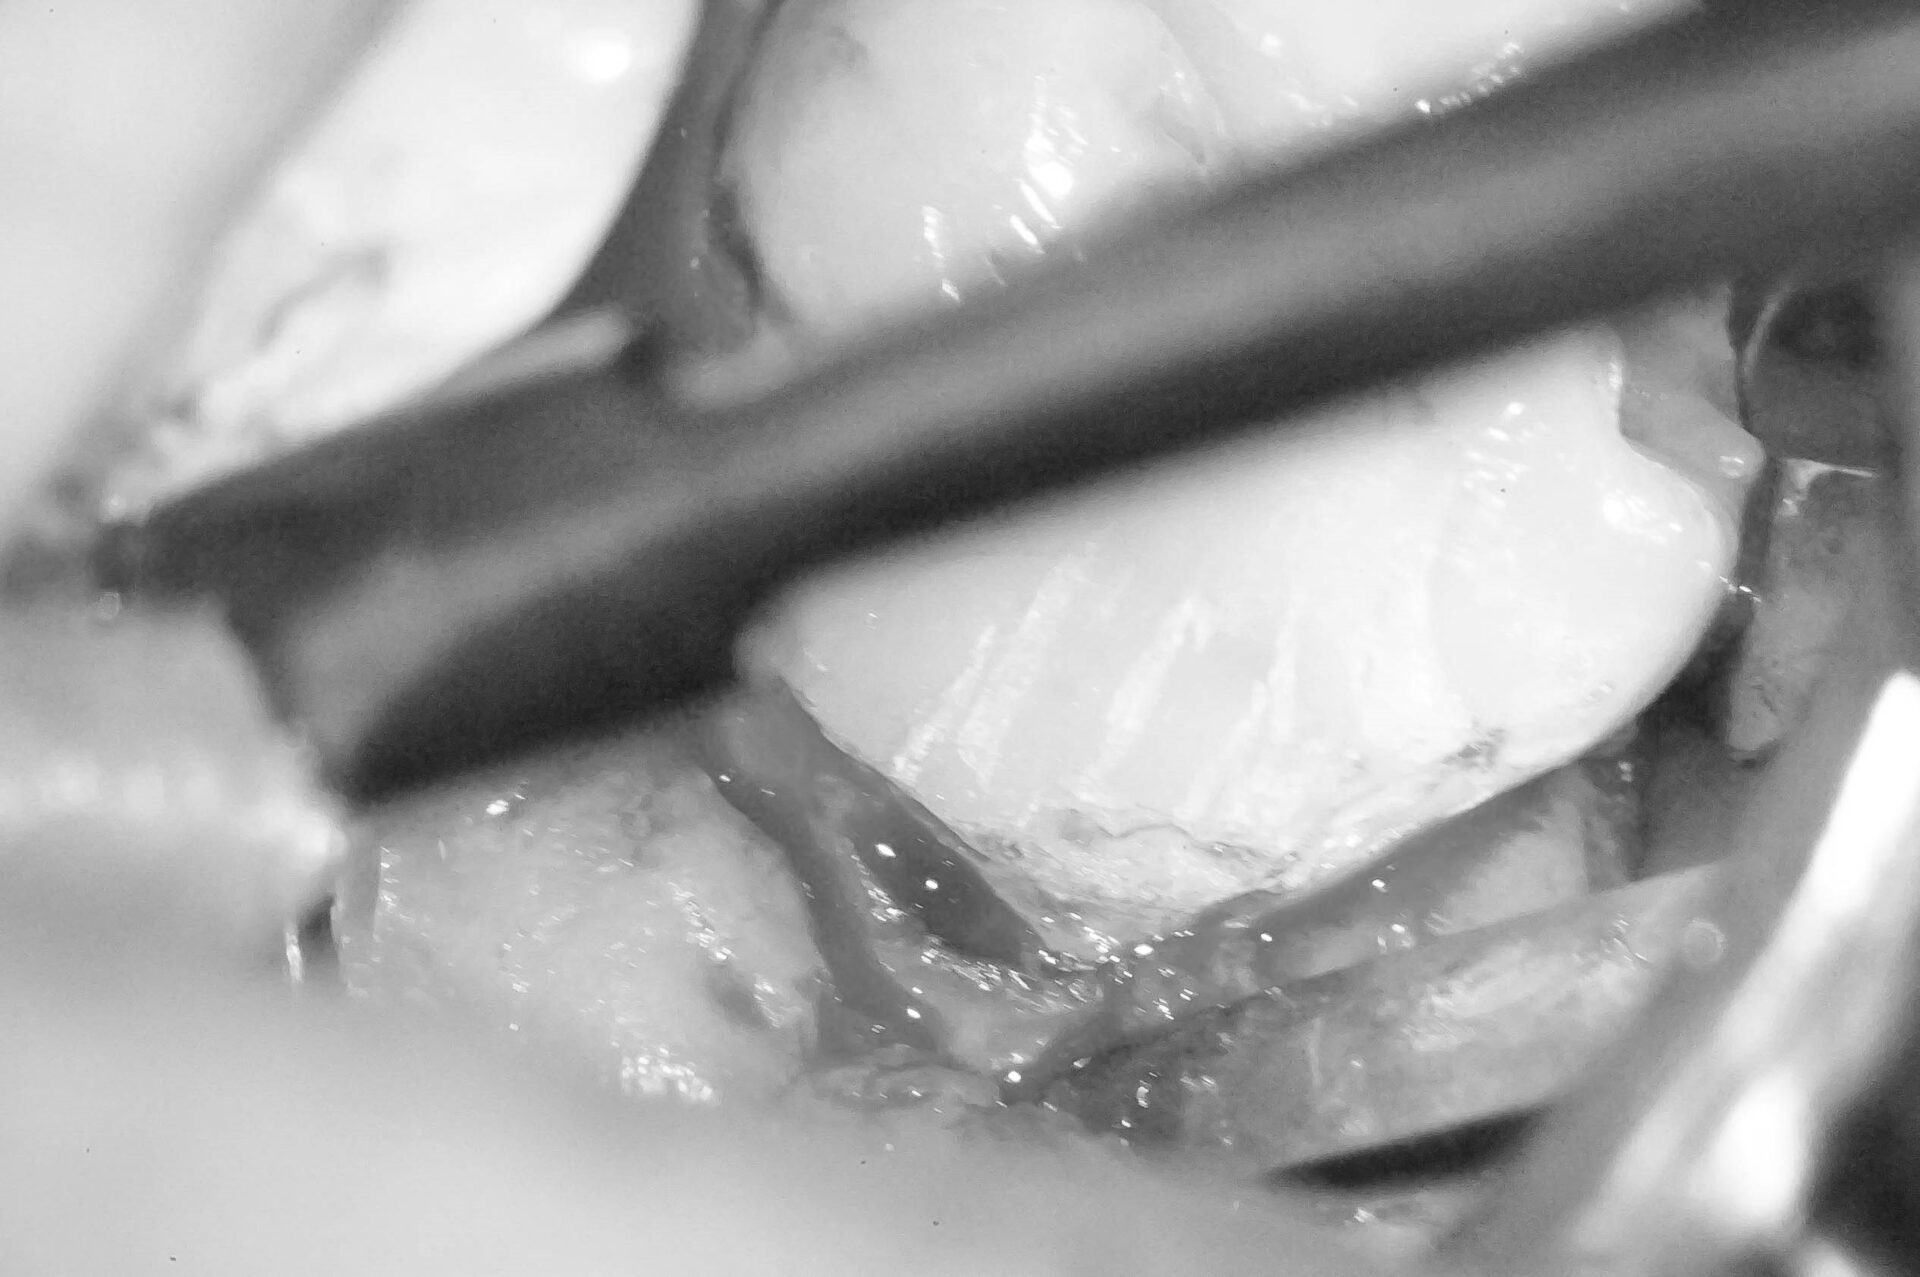

歯肉縁下ダイレクトボンディングを行った症例治療方法03

写真では分かりづらいですが、歯肉に隠れている部分に大きめのウ蝕が広がっていたので歯周外科処置を行い、視野を確保します。

レーザーで歯肉を焼き切って治療をする方法もありますが、レーザーで焼いてしまうと大きな歯肉退縮を引き起こします。

※画像はモノクロ加工しています。